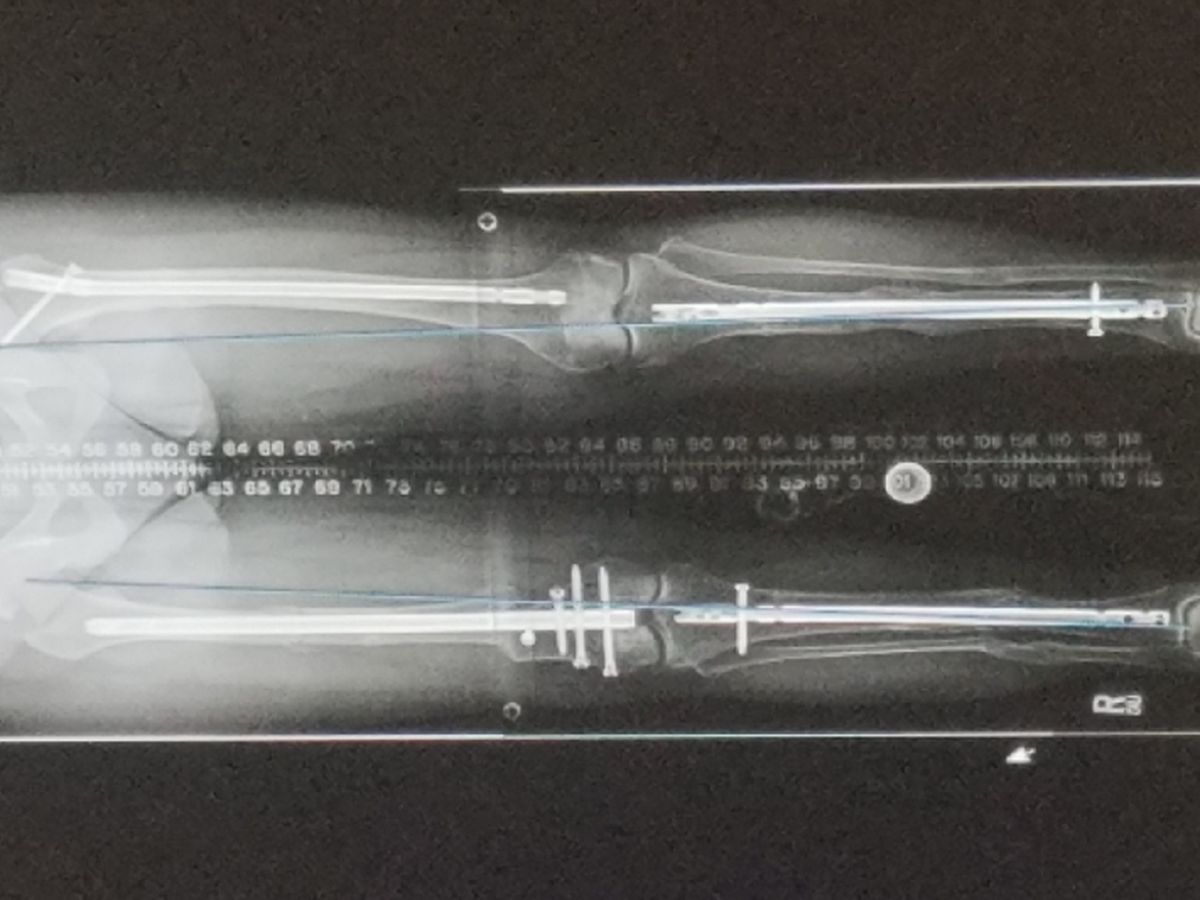

Dear friends, friends of friends, and future friends: Over the last 21 years I've had about as many surgeries. One stops counting after a while in the hopes they'll become less frequent and--dare to dream!--STOP. They haven't. [But I'm totally keeping the dream alive!] I'm actually drafting this letter in a hospital bed, freshly medically upgraded; this newest procedure the catalyst for my request for help as I (very) recently came to the realization that I work only to pay my medical bills, just managing to get by from surgery to surgery. I had never stopped to think about it in such finite terms because it's my life, my normal, and we all have our own normal. But my last 4 surgeries--including this brand spanking new one--came backtobacktobacktoback leaving me no time to catch up (physically/mentally/financially/every which way). And now I find myself falling behind after working so hard not to--with more post-op bills heading my way even as I type this. Backstory: I have a rare musculoskeletal disorder, XLH: X-linked hypophosphatemia. One in 20,000 has the condition and cases can be either genetic or sporadic. I'm the latter, so one of the rarest of the rare, if you will. The big symptoms include lower limb deformities (multiple checks), waddling gait--like my spirit animal, the majestic penguin (check), short stature (check), bone/muscle pain and weakness (check, check and check). Those are the majors. The list of minors runs deep and I'd run out of space trying to share... Current story: $4682.50 = the out of pocket deposit that was required for the surgery I'm in the hospital for [as of 9/15/18]. I had to make a larger deposit for the surgery I had last August and I took out a loan to do so --still outstanding-- hoping my insurance would cover enough of the procedure to warrant a refund of ANY amount to me. [Spoiler: it didn't.] Next came the bills for the anesthesiologist and also the balance due to the hospital following insurance payments for my weeklong stay. Then came the required/necessary medical equipment purchases and rentals, 6 months of physio copays, ongoing RX copays, and a year’s worth of follow-up surgical appointments all in all totaling -- drumroll please -- $24,365.42. Bear in mind I've just started the post-op process all over again… For balance, a bit of awesome: It turns out I have one of the XLH-iest cases of XLH and qualified for participation in a clinical trial at Yale that started a few years back. I am one of only 134 adults who helped get the first medication specifically created for XLH approved by the FDA earlier this year! Crysvita is a gamechanger for the next gen of XLHers: they may never experience most of the heinous symptoms people my age and older lived through. [Fingers crossed.] I'm super-proud to have been a small part of this big win. And along with the tons of titanium I'm chock full of, Crysvita is helping to make my bones stronger. So although I'd prefer to never-ever (EVER) have surgery again, there's a definite comfort in knowing I'm in the best shape possible to take on whatever it is when it comes. So, dearest humans of the interwebs, please chip in if you possibly can. You'll be helping to quite literally keep me on my feet! With more appreciation than you can imagine, Perrie Rizzo